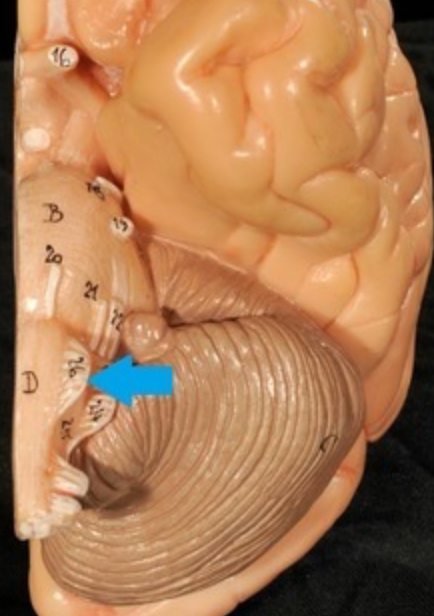

Cerebellum